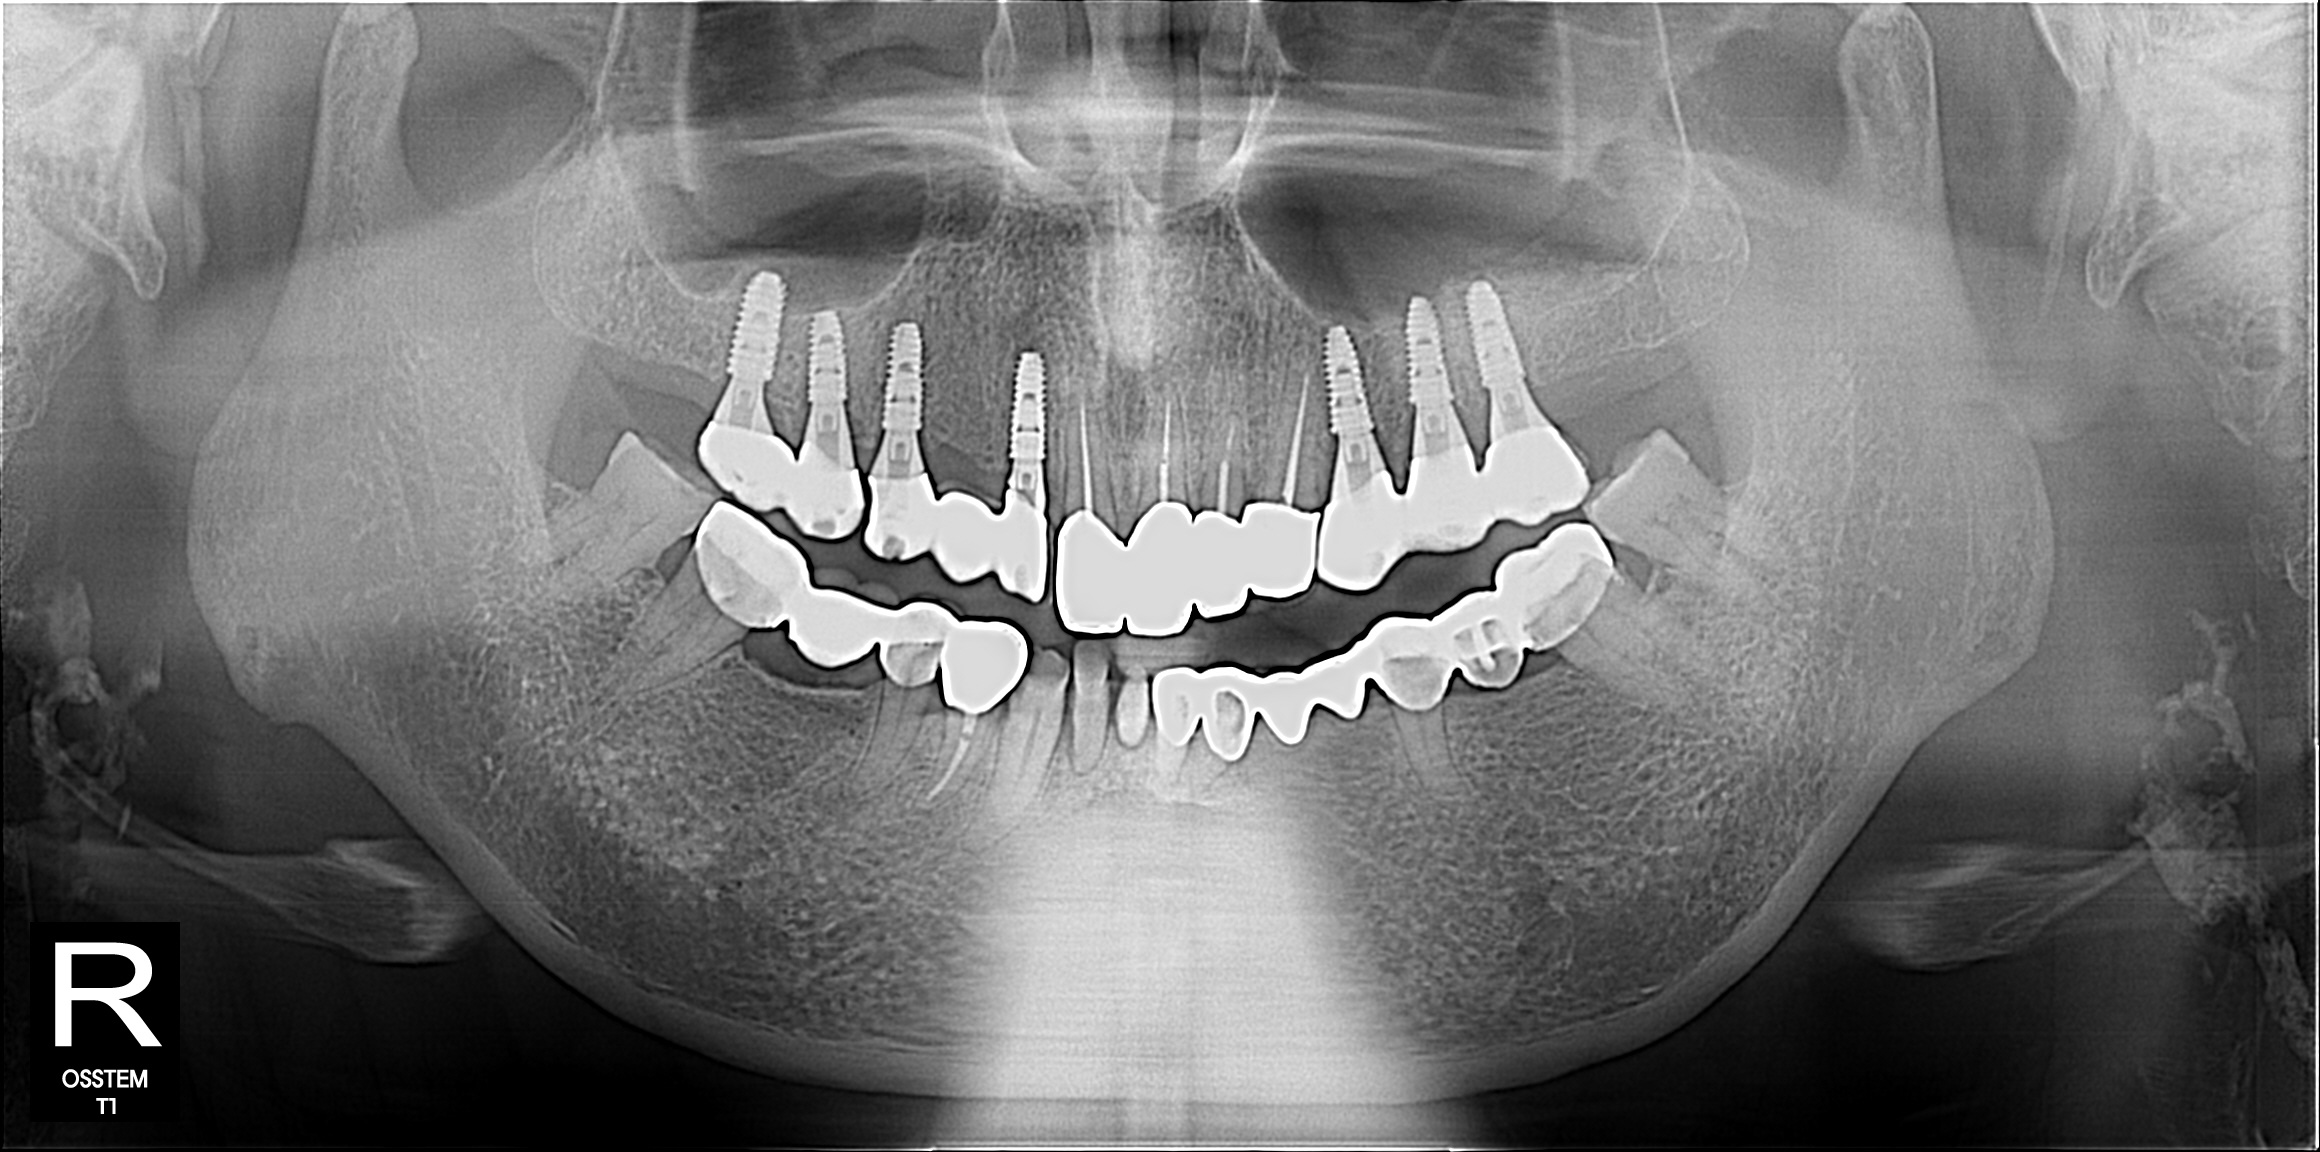

임플란트

BEFORE & AFTER